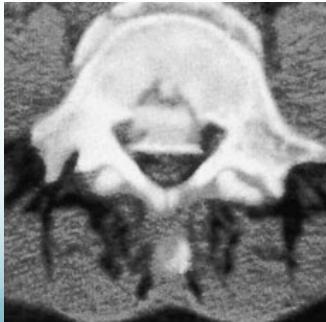

Burst Injury L-Spine

- Axial compression: shattered vertebral body

- Posterior fragments into spinal canal

- Usually unstable

- CT required

Burst Injury Classification

Is this a compression or a burst fracture?

- A burst fracture

- Why?

- Posterior displacement

Neurological Injuries